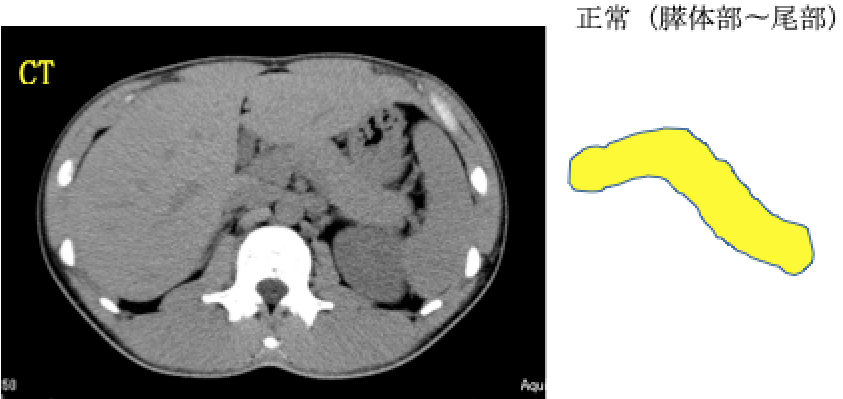

① 正常